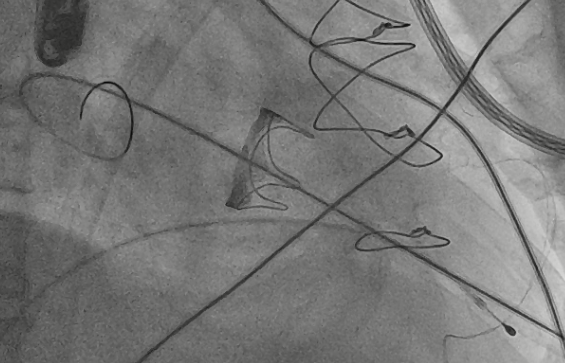

术中影像监护与评估(DSA&TEE)

猪尾导管过瓣环平面进左心房

交换加硬导丝

扩张鞘预扩心尖穿刺点

输送器进入左室至生物瓣下方